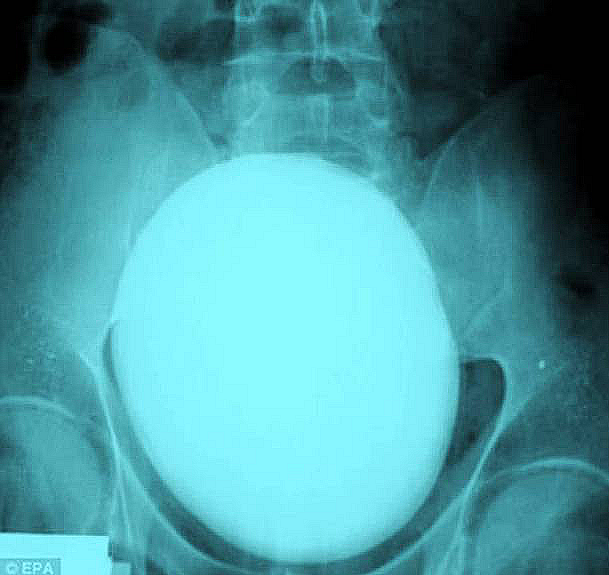

A knife

A teenager from London was stabbed in the head while trying to stop a robbery in a local shop back in 2008. Can you believe that the boy not only survived but made a full recovery as well? Incredible!